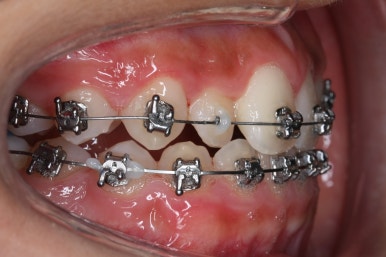

다른 앵글에서의 모습입니다.

안으로 쏙 들어가 있던 앞니가 앞으로 나오게 되면서 심미적으로 좋아지는 것을 볼 수 잇습니다.

악궁확장장치는 유지기간 이 후 다 제거가 되었고, 치아들이 매우 가지런해지는 것을 볼 수 있습니다.

이제 조금만 더 정리가 되면 장치 제거가 가능하겠네요.